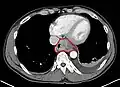

Additional testing is needed to assess how much the cancer has spread (see § Staging, below). Computed tomography (CT) of the chest, abdomen and pelvis can evaluate whether the cancer has spread to adjacent tissues or distant organs (especially liver and lymph nodes). The sensitivity of a CT scan is limited by its ability to detect masses (e.g. enlarged lymph nodes or involved organs) generally larger than 1 cm.[43][44] Positron emission tomography is also used to estimate the extent of the disease and is regarded as more precise than CT alone.[45] PET/MR as a novel modality has shown promising results in preoperative staging with fair feasibility and good correlation in comparison to PET/CT. It can enhance tissue differentiation with lowering the radiation dose to the patient.[46] Esophageal endoscopic ultrasound can provide staging information regarding the level of tumor invasion, and possible spread to regional lymph nodes.